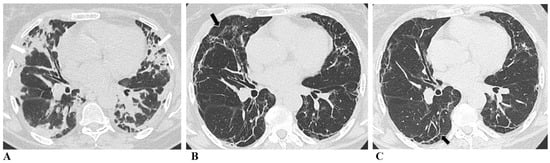

The representative radiological changes over time are shown in Figure 2.

Figure 2. Evolution of chest CT features post-COVID-19 pneumonia. (A) Chest CT at initial presentation: bilateral multifocal organizing consolidation zones predominantly in the subpleural parts of the lung parenchyma (white arrows). (B) Six-month follow-up chest CT: in place of previously seen consolidation zones, we can see septal thickening and parenchymal bands with subtle ground glass opacities (black arrows). (C) Twelve-month follow-up chest CT: we can see almost complete resorption of ground glass opacities, with persistent subpleural curvilinear parenchymal bands (black arrows).